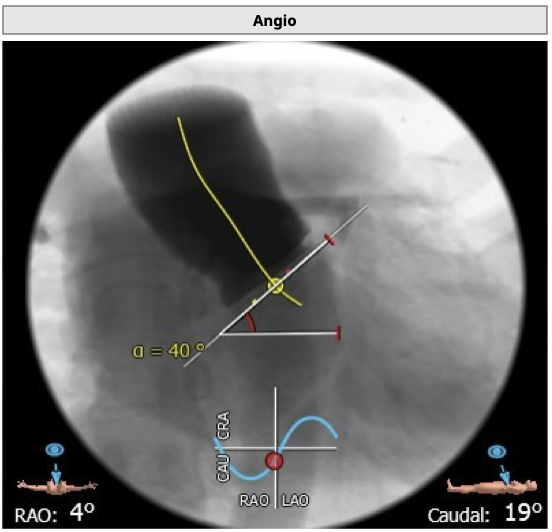

患者2007年植入HANCOCK 23号外科生物瓣,生物瓣衰败后内径为21.8 mm,术前超声评估除瓣中明显反流外,右无窦区域明显瓣周漏,综合评估,决定行血管塞封堵瓣周漏联合TAVR行瓣中瓣术式。

根据造影情况决定选择VenusA 23号瓣膜